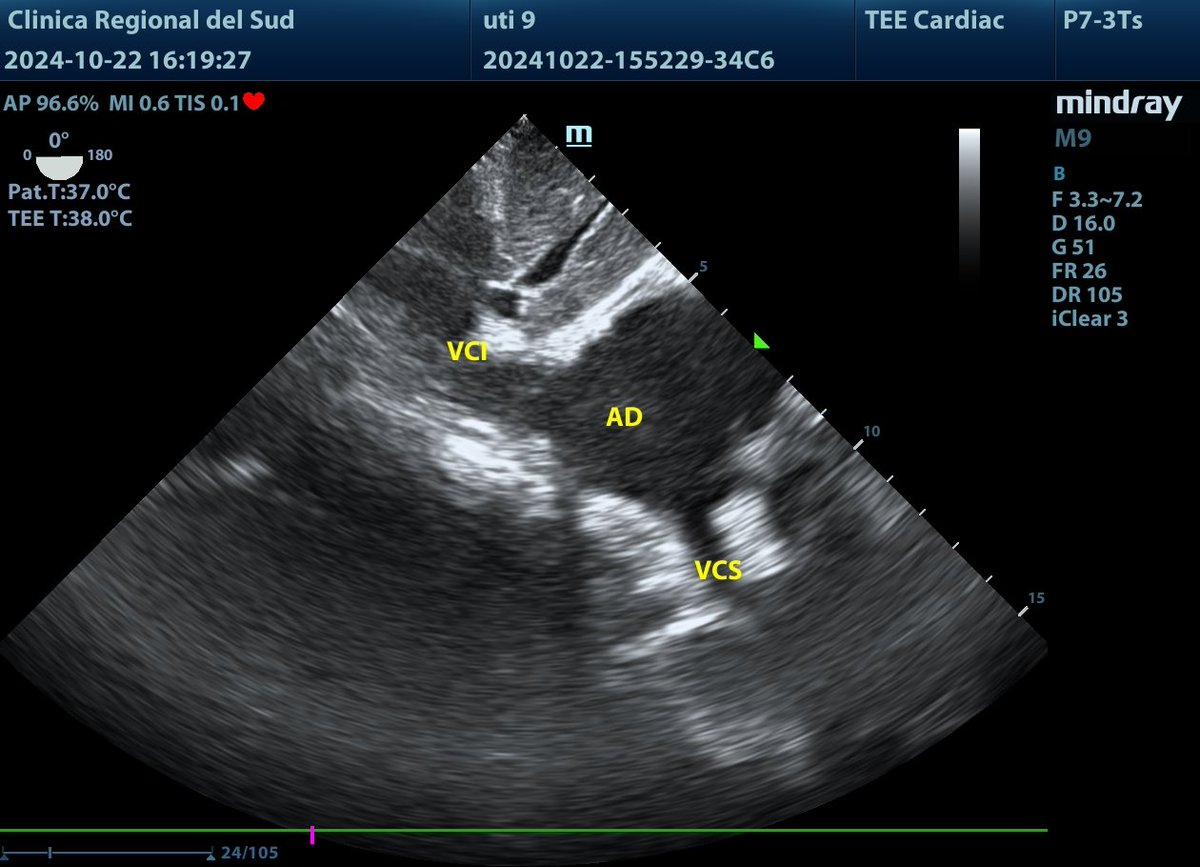

@NephroP En esa misma posición, sacando la flexión de la sonda, obtenemos esta imagen donde podemos evaluar cavidades derechas